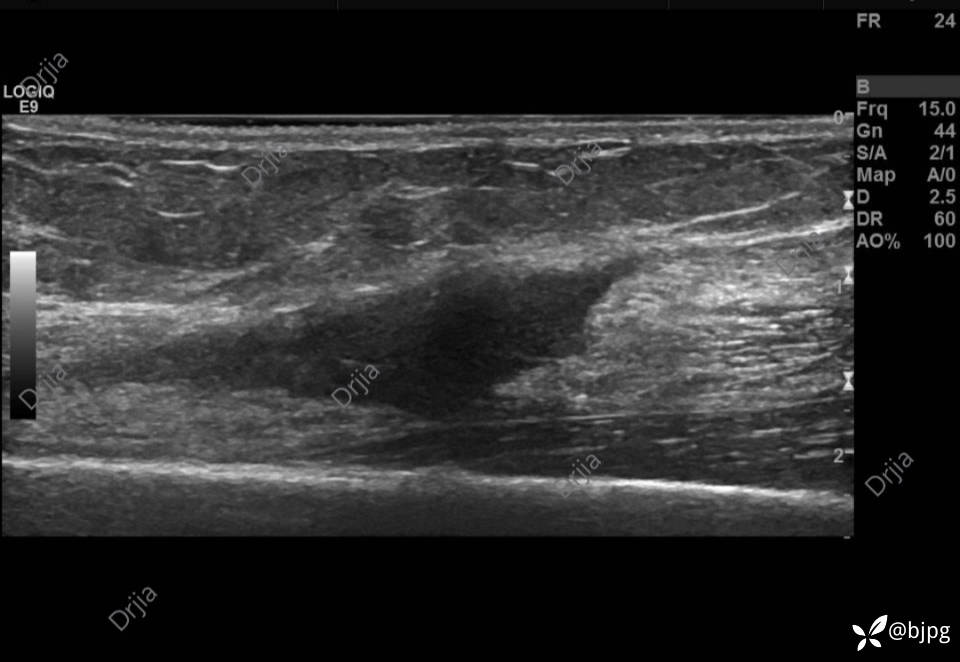

肱二头肌远心端断端血肿形成